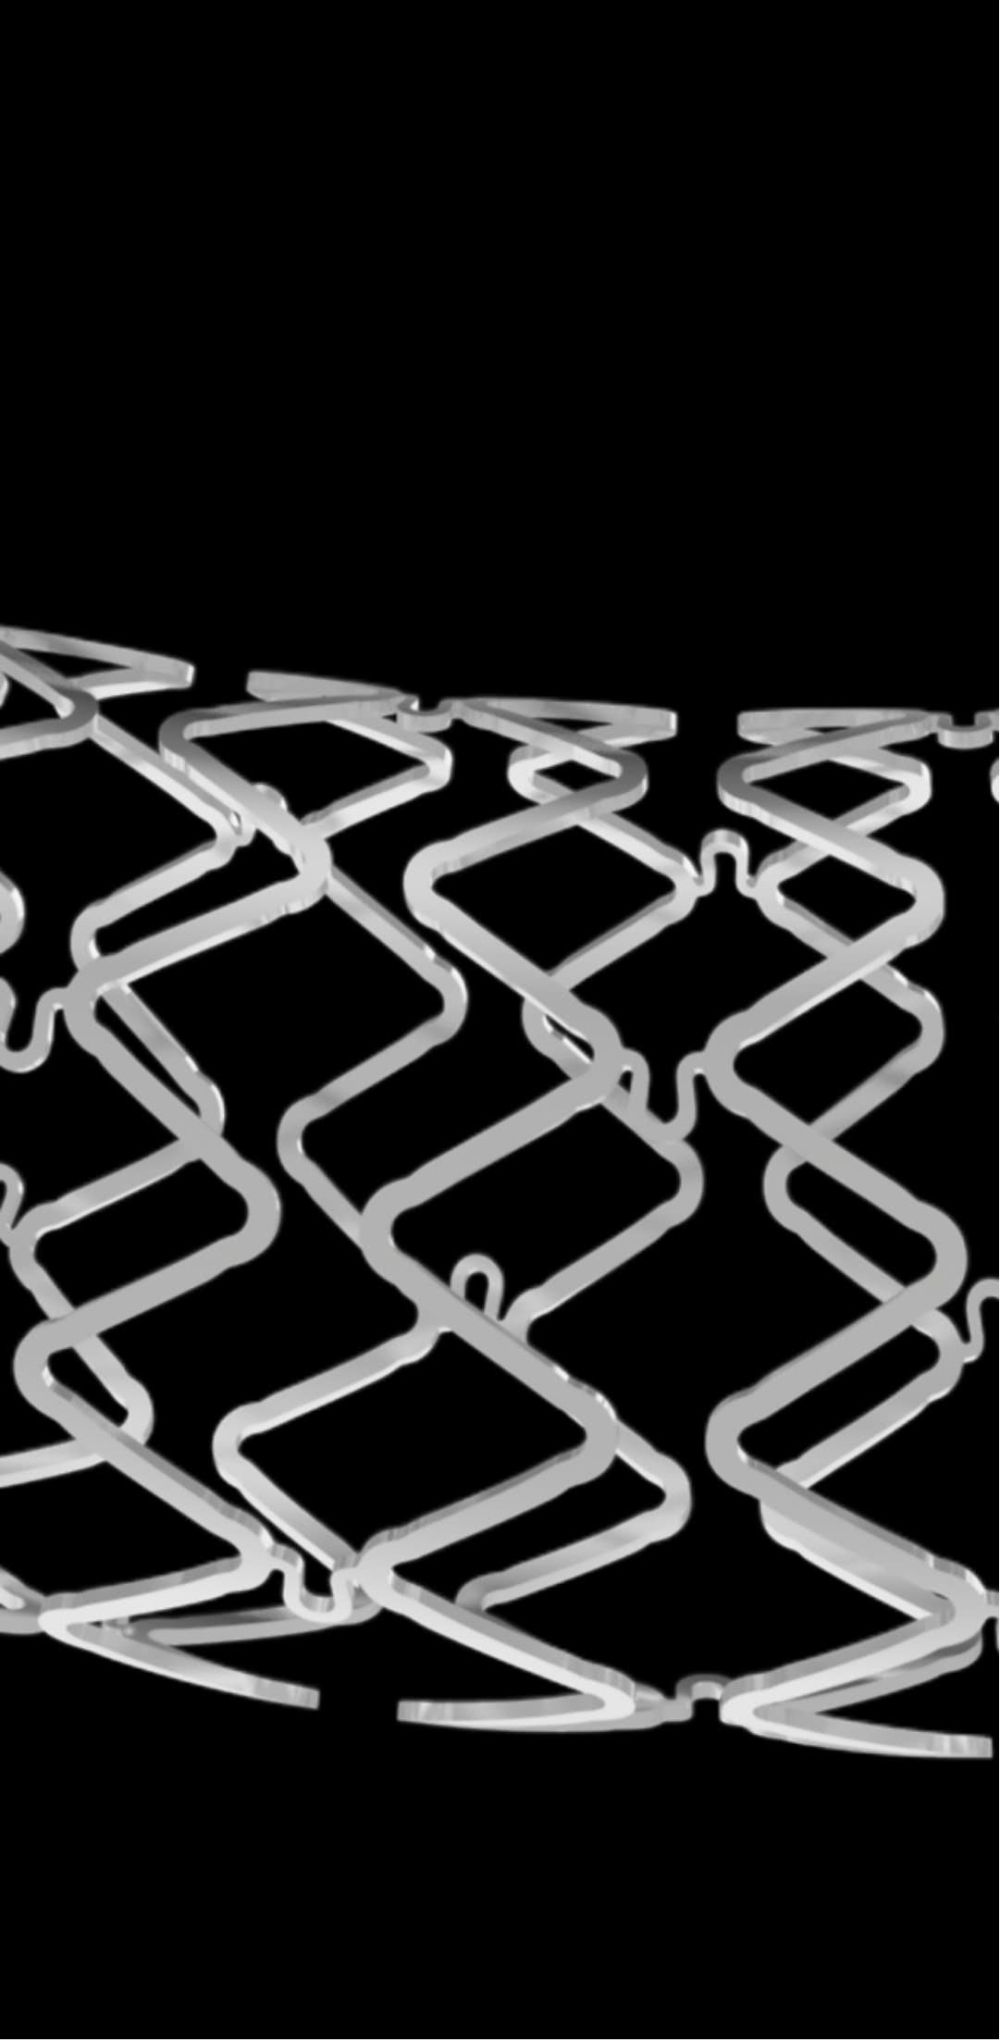

可吸收藥物洗脫支架盡管作為一種重要的研究熱點,但一直沒有很好解決可吸收材料問題。鐵基藥物洗脫可吸收外周支架采用的基材為滲入了0.05%氮的純鐵材料(Fe),所載藥物是西羅莫司。這款可吸收支架的優(yōu)勢包括:獨特的滲氮工藝使這款可吸收支架在維持足夠支撐力的同時支架壁厚可降低到60μm,支架規(guī)格豐富,最長可達118mm,專門為膝下動脈病變開發(fā);該支架通過聚乳酸(PLA)涂層載藥控制藥物釋放,能夠有效地抑制平滑肌細胞的增生和遷移;整個支架的降解周期為18-24個月。該支架是國際唯一的以鐵基為材料的全降解血管支架。